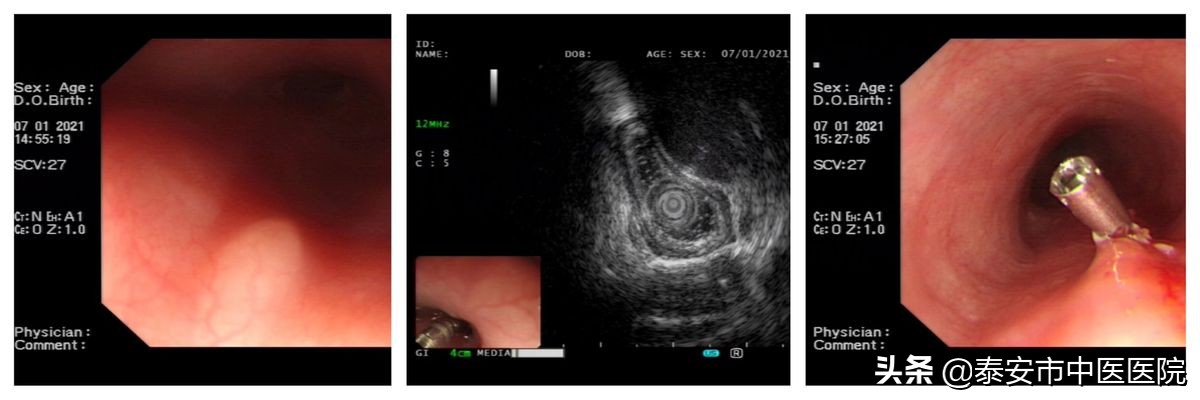

3.超声内镜使食管上端粘膜下隆起,顺利切除: